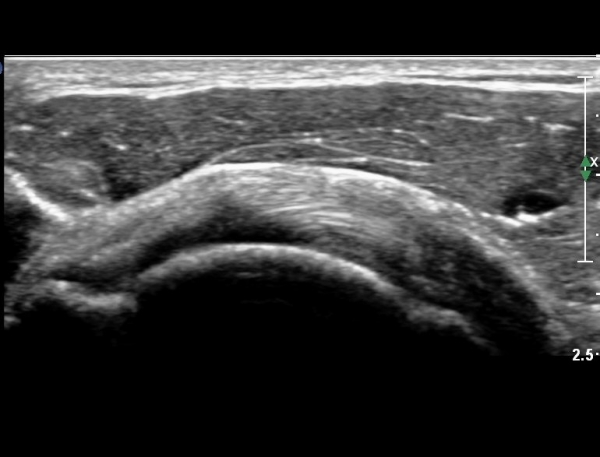

ÀÌµÎ¹Ú±Ù°Ç È¾´Ü¸é°Ë»ç¿¡¼­ °Ç ÁÖÀ§ ¼ö¾×Àú·ù µî ƯÀÌ ¼Ò°ßÀ» º¸ÀÌÁö ¾Ê¾Ò´Ù(»çÁø 1, 2)